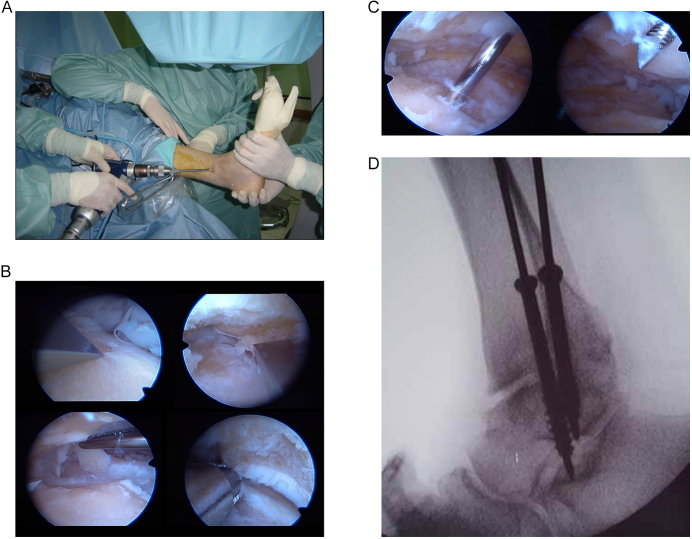

Arthroscopic ankle arthrodesis (AAA) has been performed for 40 years for end-stage ankle osteoarthritis. Along with open ankle arthrodesis (OAA) and total ankle replacement (TAR), it forms one arm of the triumvirate of commonly performed procedures for this condition. The aim of this article is to review the state of the art for AAA and compare outcomes with OAA and TAR. This narrative review of the literature traces the development of this technique through case series and systematic reviews. Traditional OAA techniques carry a nonunion rate of 11%, necessitating revision surgery in most cases. As individual and communal experience of AAA has grown, the range of pathology and deformity successfully corrected by this technique has developed. There is evidence that AAA offers greater and more rapid union rates, with reduced hospital stay and better long-term outcomes. However, the technique requires mature surgical skills and still carries a significant complication rate. No single procedure is suitable for all patients. AAA can be seen as the new gold standard for patients with isolated ankle osteoarthritis and no/minimal deformity, either within the talocrural joint or hindfoot or patients with systemic and/or local comorbidities that would benefit from minimal disturbance to the soft-tissue envelope. However, in older patients, the presence of concomitant hindfoot osteoarthritis or significant deformity, TAR and OAA remain valuable procedures in the foot and ankle surgeon's armamentarium.